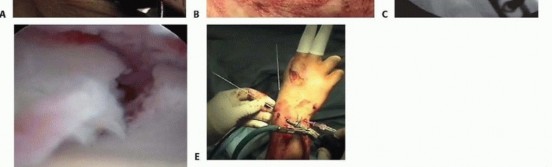

arthroscope is approximately 2.7 mm in diameter, and even smaller scopes may be used if desired. In addition, a small joint shaver (3.5 mm or less) is useful to clear fracture debris and hematoma. The ideal timing for arthroscopic-assisted fixation of distal radius fractures is 3 to 10 days following injury. 13 Earlier attempts at fixation may be complicated by soft tissue swelling and troublesome bleeding, obscuring visualization. After 10 days, the fracture fragments start to become sticky and more difficult to percutaneously elevate and reduce. ## Positioning Arthroscopic-assisted fixation of distal radius fractures may be performed with the arm suspended vertically in a traction tower, horizontally in a traction tower, or with finger traps applied attached to weights hanging over the edge of the hand table. Wrist arthroscopy in the horizontal position may make it easier to simultaneously monitor the reduction fluoroscopically and place hardware. However, it does not allow for simultaneous volar access to the wrist. Suspending the wrist in a vertical position with a traction tower allows simultaneous access to both the volar and dorsal aspects of the wrist. This is particularly useful when wrist arthroscopy is used as an adjunct to volar plate fixation of the distal radius fracture. A new traction tower has been designed to allow simultaneous evaluation of the intra-articular reduction of the distal radius arthroscopically and fluoroscopically ( FIG 2A). The surgeon may stabilize a comminuted fracture of the distal radius with a plate, and simultaneously evaluate the articular reduction arthroscopically. The traction tower allows for traction of the wrist in either the vertical or horizontal planes, depending on the surgeon's preference ( FIG 2B). ## Approach The wrist is suspended in a traction tower, and the standard dorsal 3-4 viewing portal, 4-5 or 6R working portal, and 6U inflow portal are made.

### FIG 2 • A. This traction tower uses a suspension bar at the side rather than at the center of the wrist. This allows easy fluoroscopic evaluation of the fracture reduction, with simultaneous full access to the volar and dorsal aspects of the wrist. B. The tower can be flexed into a horizontal position for surgeons who prefer to treat distal radius fractures in that position. It is difficult to palpate the normal extensor tendon landmarks for traditional wrist arthroscopy in patients who sustain a fracture of the distal radius because of swelling. 17 However, the bony landmarks usually can still be palpated. These bony landmarks include the bases of the metacarpals, the dorsal lip of the radius, and the ulnar head. The 3-4 portal is made in line with the radial border of the long finger. It is very useful to place an 18-gauge needle into the proposed location of the 3-4 portal before making a skin incision. If the portal is placed too proximal, the arthroscope may be placed within the fracture pattern itself. If it is placed too distal, it can injure the articular surface of the carpus. Once the precise ideal location of the portal is located, the portal is made by pulling the skin with the surgeon's thumb against the tip of a no. 11 blade. Blunt dissection is carried down with a hemostat, and the arthroscope, with a blunt trocar, is introduced into the dorsal 3-4 portal. This technique decreases potential injury to cutaneous nerves. Thorough irrigation of the joint is necessary to wash out fracture hematoma and debris and improve visualization. Inflow may be provided through the arthroscope cannula or separately through a 14-gauge needle into the 6U portal. Use of a separate 6U inflow portal is recommended. The small joint arthroscopy cannula does not allow as much space between the cannula and the arthroscope, limiting the amount of flow through the cannula. Outflow to the wrist is provided through intravenous extension tubing connected to the arthroscope cannula. The 4-5 working portal is made in line with the mid-axis of the ring metacarpal. Alternatively, the 6R working portal is made just radial to the palpable extensor carpi ulnaris tendon. An 18-gauge needle is placed into the joint and should lie just distal to the articular disc. A 4-5 or 6R portal usually is located just proximal to the 3-4 portal because of the natural radial slope of the distal radius.

TECH FIG 1 • A. Arthroscopic view of the patient whose radiographs are seen in FIG 1. The arthroscope is in the 6R portal looking across the wrist, and a blunt trocar is in the 3-4 portal. The displaced radial styloid fragment is well visualized. B. A combination of joysticks inserted into the radial styloid fragment and a trocar inserted into the 3-4 portal allows anatomic reduction of the displaced radial styloid fragment and radiocarpal joint. C. The radial styloid fragment is anatomically reduced (with no residual rotation) and stabilized. D. PA view demonstrating anatomic reduction to the radial styloid fragment. Headless cannulated screws are used, if possible, to avoid soft tissue irritation. E. Lateral view showing anatomic restoration to the radial styloid fragment and restoration of the carpus in line with the radius. Suspend the wrist in a traction tower and establish the standard arthroscopic portals. Insert the scope in the dorsal 3-4 portal and clear the joint of debris and hematoma. Transfer the arthroscope to the 6R or 4-5 portal to look across the wrist and effectively judge rotation and reduction of the radial styloid fragment. Using the previously placed guidewires as joysticks, manipulate and anatomically reduce the fracture fragment under direct arthroscopic observation. A trocar can be inserted through the 3-4 portal to help further guide the reduction of the radial styloid fragment ( TECH FIG 1A,B).

### TECH FIG 2 • A. PA view showing an impacted scaphoid facet fracture fragment with an obvious injury to the SLIL. B. Lateral view showing a dorsal rim fracture fragment. C. The arthroscope is in the 6R portal, demonstrating the impacted scaphoid facet fracture fragment. This would be quite difficult to view through an open arthrotomy but is well visualized arthroscopically under bright light and magnified conditions. D. The impacted scaphoid facet fragment is elevated back to the volar rim, using the rim as a landmark to judge rotation. E,F. Geissler grade III tear involving the SLIL as seen through the 3-4 portal (E) and the radial midcarpal portal (F).(continued) Suspend the wrist in the traction tower, establish portals, and evacuate the fracture debris and hematoma. The depressed lunate facet fragment is best seen with the arthroscope in the 3-4 portal ( TECH FIG 2C,D). Percutaneously place an 18-gauge needle directly over the depressed fragment as viewed arthroscopically. Insert a large K-wire about 2 cm proximal to the previously placed 18-gauge needle to percutaneously elevate the depressed lunate facet fragment.

* Open Reduction and Stabilization Perform a standard volar approach, and do not open the radiocarpal joint capsule ( TECH FIG 4A). The radial styloid fragment and the volar ulnar fragment are reduced to the shaft under direct visualization. The radial styloid fragment is provisionally pinned.*

### TECH FIG 4 • A. A standard volar approach is made, centered over the flexor carpi radialis tendon, and the fracture site is exposed. B. A volar distal radius locking plate is applied. The initial screw is placed through the proximal plate to secure the plate to the shaft. C. The intra-articular reduction is viewed under fluoroscopy and provisionally pinned. A displaced intra-articular fracture fragment can still be identified. D. The arthroscope is in the 3-4 portal, showing the volar capsule blocking reduction of the radial styloid fragment. E. Joysticks previously inserted into the radial styloid fragment are then used to control and anatomically reduce the radial styloid fragment. F. The arthroscope is in the 6R portal looking across the wrist. Anatomic reduction of the radial styloid fragment is documented. G. Once the anatomic restoration of the articular surface is evaluated both arthroscopically and fluoroscopically, the distal screws are placed in the plate. H. Fluoroscopic view showing anatomic restoration to the articular surface of the distal radius. I. The patient had an associated osteochondral fracture of the lunate, not visible on plain radiographs. The displaced fragment is arthroscopically removed.

Apply a volar distal radius locking plate to stabilize the volar bone fragments ( TECH FIG 4B). Place a screw in the proximal portion of the plate first to reduce the plate to the shaft. Provisionally pin the distal fragments through the plate. Manipulate the articular fragments under fluoroscopy to obtain as anatomic a reduction as possible ( TECH FIG 4C,D). Suspend the wrist in the traction tower and reduce the articular fragments arthroscopically ( TECH FIG 4E,F). If articular reduction is not anatomic, remove the pins and fine-tune the reduction. Once the fracture reduction is thought to be anatomic, place the distal screws through the plate ( TECH FIG 4G-I). It is important that the fracture be reduced to the plate, with no gap between the plate and the bone. This can be achieved by flexion of the wrist in the tower and by insertion of a nonlocking screw first, before the insertion of standard locking screws. Place the remaining proximal and distal screws if the reduction is anatomic under both fluoroscopy and arthroscopy. 1. ### Reduction and Stabilization of a Dorsal Die-Punch Fragment It is not possible to see the reduction of a dorsal die-punch fragment through the volar approach when stabilized with a plate. Arthroscopy can be helpful in this scenario. Insert the volar plate as previously described and provisionally fix the device to the radius. Frequently, the dorsal fragment may still be slightly proximal in relation to the radial shaft. The dorsal die-punch fragment is best seen with the arthroscope in the 6R portal. Establish the volar radial portal between the radioscaphocapitate ligament and the long radiolunate ligament, as viewed directly through the previous performed volar approach. 23 Percutaneously elevate and anatomically reduce the dorsal diepunch fragment as viewed arthroscopically. Once this has been achieved, place the screws into the plate and observe their path arthroscopically to ensure adequate stabilization of the dorsal die-punch fragment. 2. ## Ulnar Styloid Fractures Following anatomic reduction of the distal radius fracture, insert the arthroscope in the dorsal 3-4 portal and the probe in the 6R portal. Palpate the tension of the articular disc. Good tension indicates that the majority of the peripheral TFCC fibers are intact or still attached to the proximal ulna. A peripheral tear of the articular disc is repaired arthroscopically when detected. 30 Stabilization of a large ulnar styloid fragment is considered when the articular disc is lax by palpation and no peripheral TFCC tear is identified ( TECH FIG 5). In this instance, the majority of the fibers of the TFCC are attached to the displaced ulnar styloid fragment. Make a small incision between the extensor carpi ulnaris and the flexor carpi ulnaris tendons and identify the fracture site. Retrieve the distal fragment, which often displaces in a distal and radial direction. Mobilize the styloid fragment using a no. 15 blade, taking care to protect the TFCC insertion. Reduce the fragment anatomically, under direct visualization, and insert a guidewire in a retrograde manner for provisional stability. Stabilize the ulnar styloid fragment using either a tension band technique (with wire and two K-wires) or, preferably, using a micro headless cannulated screw. Place the cannulated headless screw over the guidewire and verify fracture reduction with fluoroscopy. Insert the arthroscope into the 3-4 portal and the probe into the 6R portal to document restoration of TFCC tension.